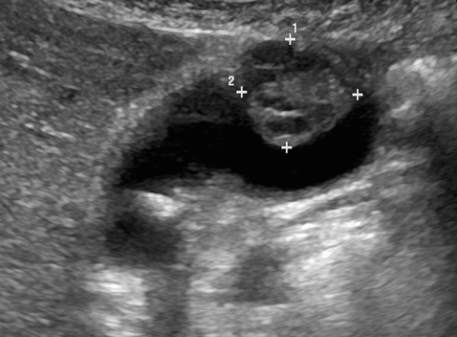

US finding

- 담낭벽 석회화에 의한 소견으로 후방음향음영을 동반한 곡선모양의 고에코를 나타내는 것

- 전벽과 후벽 모두 고에코를 나타내는 것

- 음향음영을 동반하는 불규칙한 고에코가 군집형태를 이루는 것 (암의 가능성이 높다)

- 환자 체위에 따른 변화가 보이지 않는다

- 담낭 내강을 관찰하기 어렵다